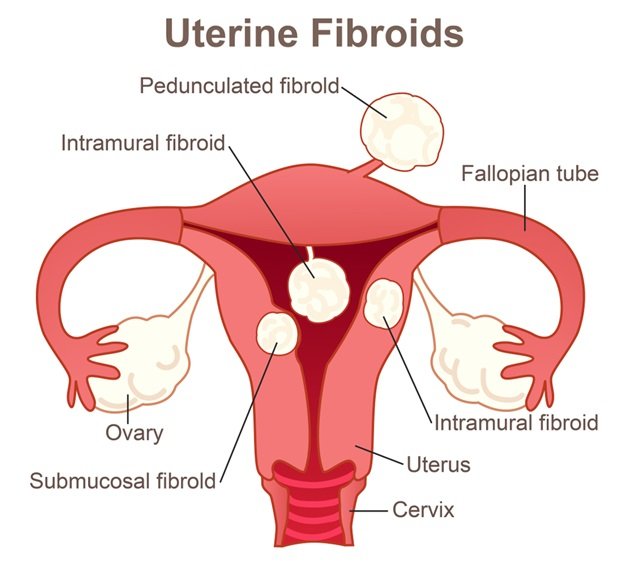

Types of Uterine Fibroids – Dr Pamela Tan | Uterine fibroids, Fibroids …

FIGO classification of uterine fibroids according to | Download …

Uterine fibroids. Fibroid types and uterine fibroids treatment | MED Expert

Uterine fibroids – The Lancet